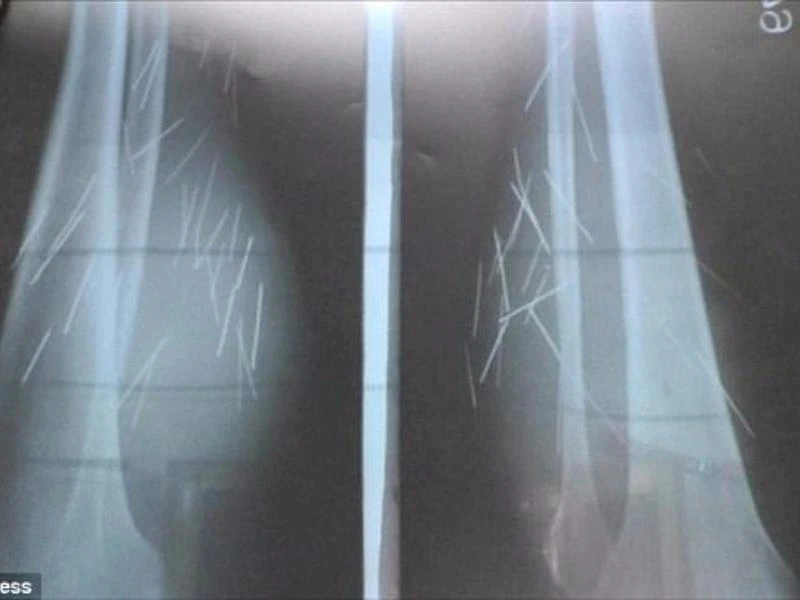

Phim chụp X-quang cho thấy có rất nhiều kim, đinh trong chân Devi. Ảnh: Cover Asia Press

Trước đó, cô Devi từng đi nhiều nơi để điều trị chứng bệnh kỳ lạ của mình nhưng các BS đều lắc đầu từ chối. Đến tận hôm 25-10 vừa rồi, sau khi khám bệnh tại bệnh viện chính phủ, các BS mới tìm ra được nguyên nhân. Họ tiến hành phẫu thuật và lấy tất cả số kim loại đó ra khỏi người Devi. Theo các BS, có ba loại vật nhọn bên trong cơ thể Devi là kim tiêm, kim khâu và đinh nhọn. Tổng cộng có đến 70 mẩu kim loại như vậy bên trong chân của Devi.